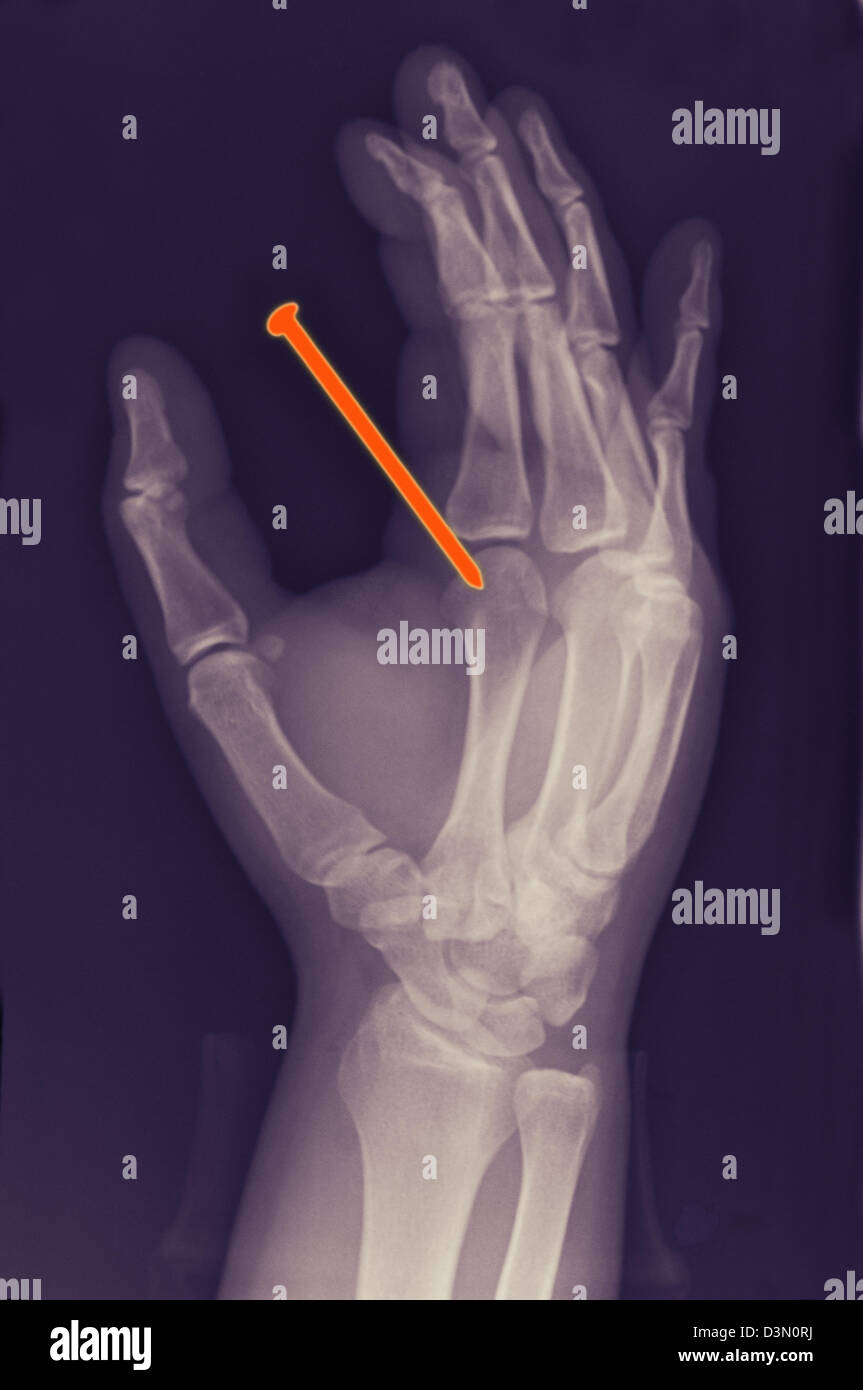

hand xray of a 26 year old man who accidentally shot a nail from a Nail Gun Through Finger Nail gun injuries, common in the construction industry, are usually puncture wounds on the hands and fingers, but sometimes they result in. The guidance highlights what is known about nail gun injuries, including the parts of the body most often injured and the types of severe injuries. Most injuries to the nail arise from one of three mechanisms. Evaluation and. Nail Gun Through Finger.

hand xray of a 26 year old man who accidentally shot a nail from a Nail Gun Through Finger Accidental discharge, careless handling of equipment, overpenetration of structures by the nail, ricochet or shattering of the nail, or structural unsoundness of the receiving. Penetrating injuries cause considerable pain and discomfort to the patient, effective analgesia needs to be provided to allow removal of object, investigations and cleaning of the wound. Nail gun injuries, common in the construction industry, are. Nail Gun Through Finger.